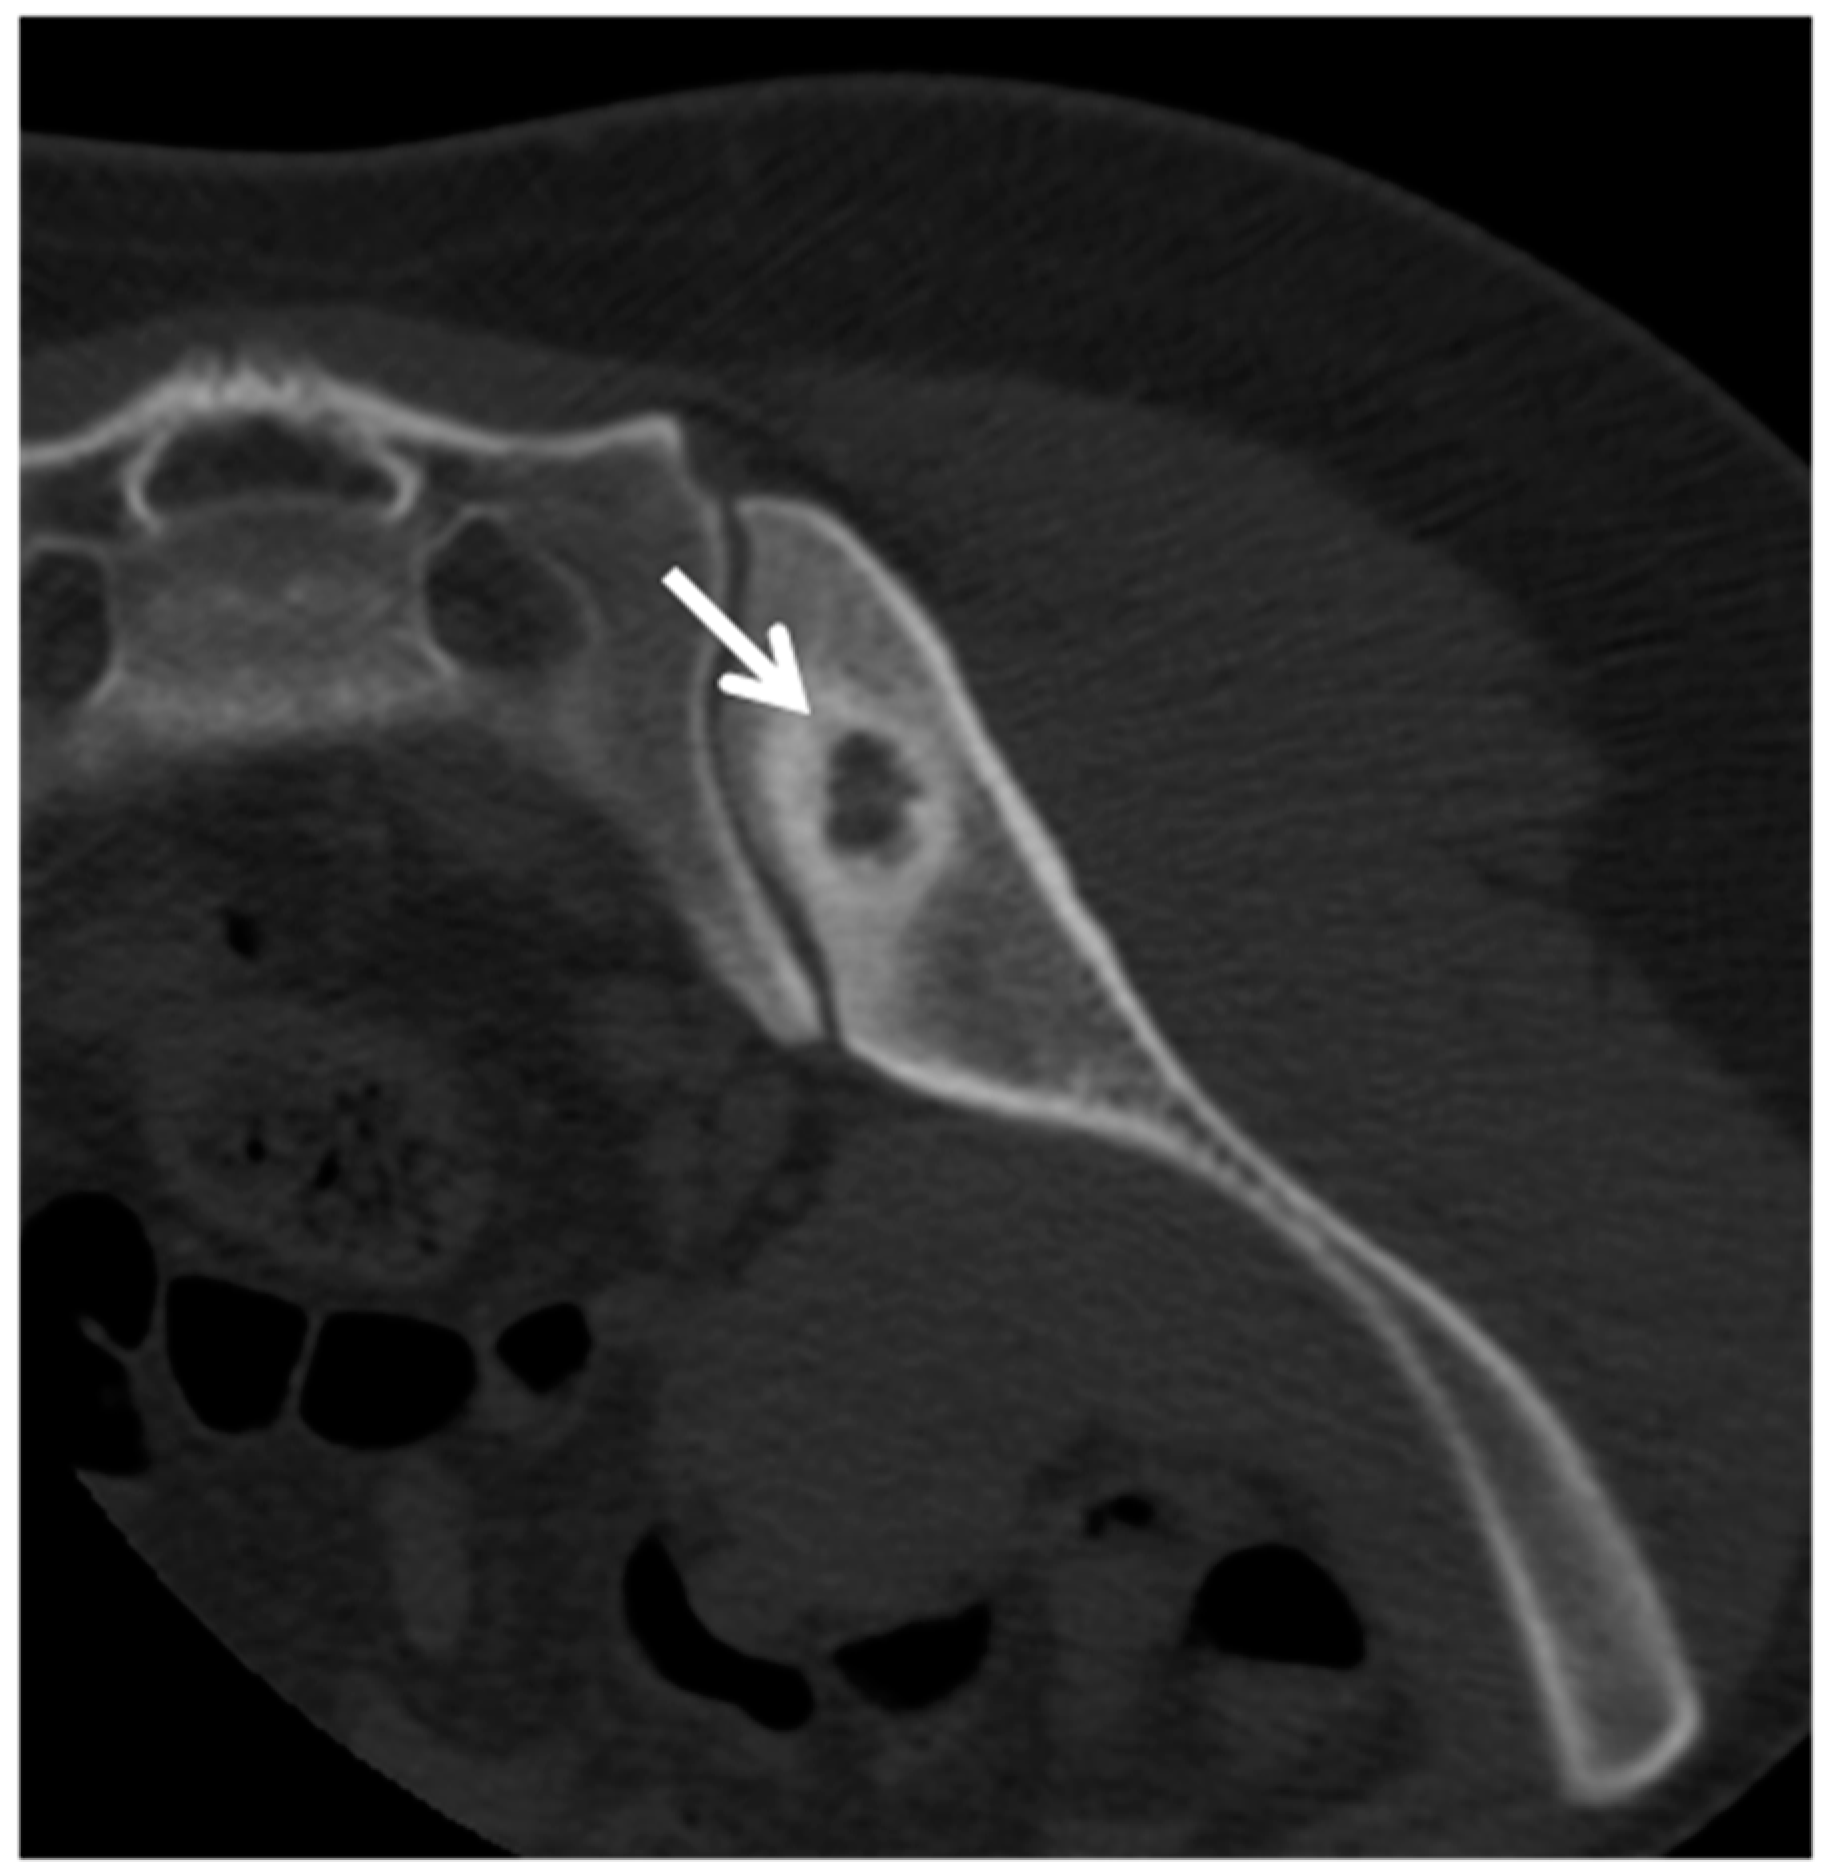

- Michel, S.C.; Pfirrmann, C.W.; Boos, N.; Hodler, J. CT-guided core biopsy of subchondral bone and intervertebral space in suspected spondylodiskitis. AJR Am. J. Roentgenol. 2006, 186, 977–980. [Google Scholar] [CrossRef] [PubMed]

- Rimondi, E.; Rossi, G.; Bartalena, T.; Ciminari, R.; Alberghini, M.; Ruggieri, P.; Errani, C.; Angelini, A.; Calabrò, T.; Abati, C.N.; et al. Percutaneous CT-guided biopsy of the musculoskeletal system: Results of 2027 cases. Eur. J. Radiol. 2011, 77, 34–42. [Google Scholar] [CrossRef]